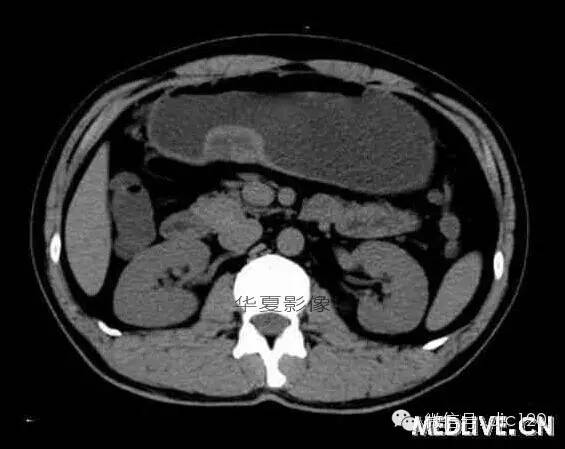

男,36歲,間斷性返酸噯氣3年,3個月前出現(xiàn)上腹疼痛,饑餓時加重。圖1-3為CT平掃,圖4-6分別為CT增強(qiáng)掃描的動脈期、門脈期和延遲期。

CT檢查可見胃幽門前區(qū)胃小彎側(cè)胃壁局限性增厚、隆起或伴凸向胃腔內(nèi)的小結(jié)節(jié)灶,寬基地,境界光整,注射對比劑,增強(qiáng)掃描后,CT值可達(dá)50HU以上,與正常胰腺強(qiáng)化相仿。

胃迷走胰腺大多位在距幽門1-6cm的胃竇胃大彎側(cè),粘膜下層內(nèi),為1-3cm大小的病灶。 與胃壁以寬基底相,增強(qiáng)掃描病灶表面覆蓋的黏膜明顯強(qiáng)化且連續(xù),病灶內(nèi)無明顯壞死,病變強(qiáng)化方式類似于正常胰腺組織;當(dāng)病灶出現(xiàn)邊緣臍凹征或中央導(dǎo)管征時,對EP的診斷具有一定的特異性。